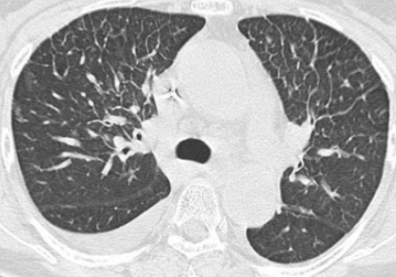

图6 16岁男性诊断移植后OP

回顾性研究[23]发现HSCT后间质性肺疾病(ILD)对应几种组织学模式,如OP和非特异性间质性肺炎、弥漫性肺泡损伤、淋巴细胞性间质性肺炎和胸膜实质性肺炎纤维弹性增生症。尤其需要注意的是,几乎所有病例组织学上呈现肺间质性改变与BO并存。故移植后ILD的原因不除外与环境、药物或遗传因素相关,尤其是allo-HSCT受者服用了多种可诱发ILD的药物[16]。